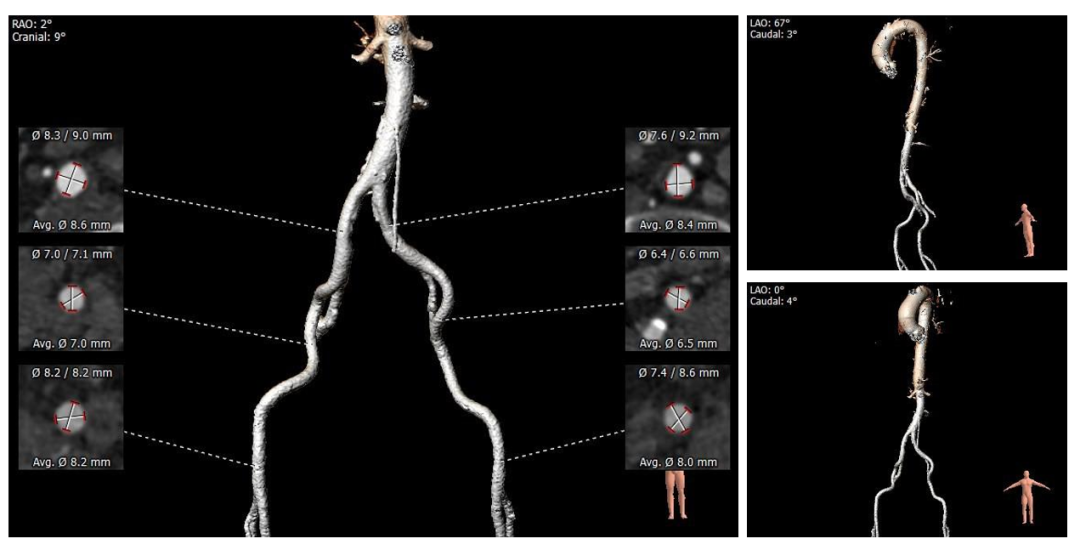

6. 双侧股髂动脉未见明显扭曲,腹主动脉存在钙化斑块,管腔内径可,整体血管条件良好。

5.外周入路走行未见明显扭曲,腹主动脉存在钙化,血管内径可,综合评估血管并发症风险不高,入路穿刺规范操作,小心通过,避免血管损伤及相关并发症。

外周血管及主动脉弓解剖